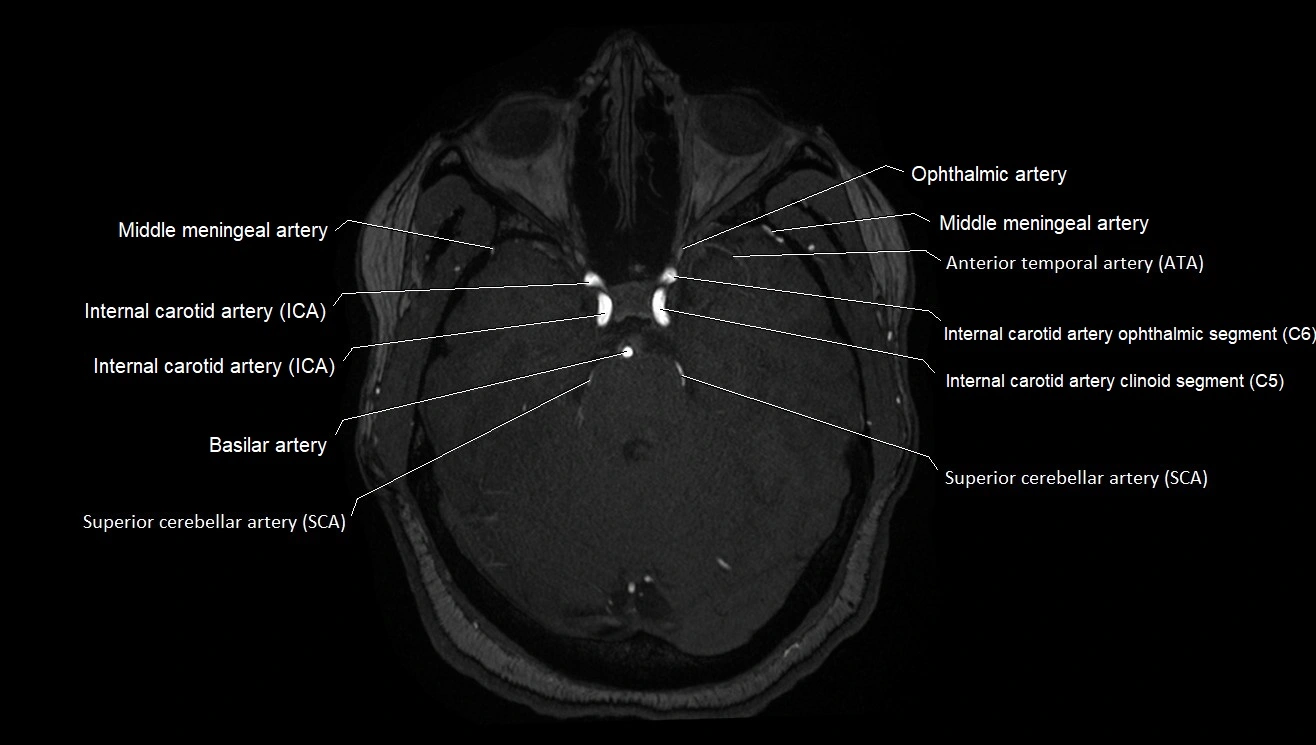

CTA (CT Angiography):

• Opacified with iodinated contrast, AChA appears as a bright high-attenuation vessel

• Visualized from ICA origin along optic tract toward choroid plexus

• 3D reconstructions depict its course and relation to adjacent arteries

• Gold standard for identifying aneurysms, occlusion, or vascular anomalies

CT images

image